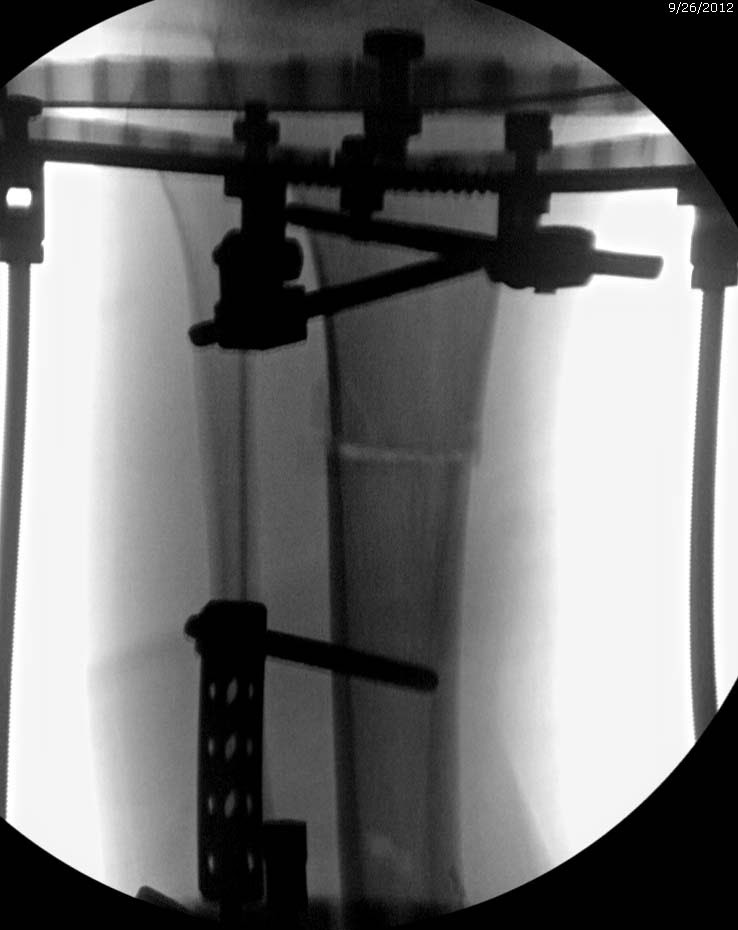

Данный случай не огнестрельная рана, а результат мотоциклетной аварии. Независимо от повреждения при таких обширных дефектах мягких и костной тканей применяется схожая тактика. Как видно, после нескольких I&D для создания “pseudo membrane” применили цилиндрический блок из цемента. Дефект мягких тканей закрыли свободным Anterior Thigh Graft. Из малого доступа цилиндр удален небольшими кусочками, а пространство заполнили бусами для освобождения пространства. По мере приближения регенерата освободили пространство удалением бус через небольшой разрез. Этап созревание регенерата можно было ускорить усилением интрамедуллярным гвоздем, но решили закончить методом Илизарова.